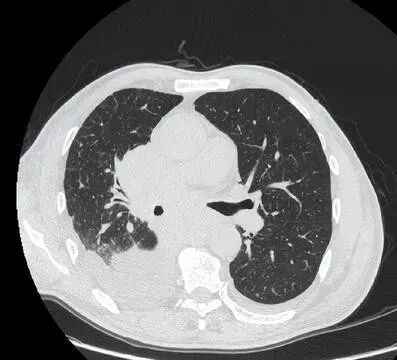

68岁患者,男,自由职业者,吸烟史50年,因喘憋咳嗽就诊,胸部CT提示肺癌,胸腔积液,淋巴结转移,非常遗憾失去手术机会,病情进展迅速,从发病到去世不足1个月。